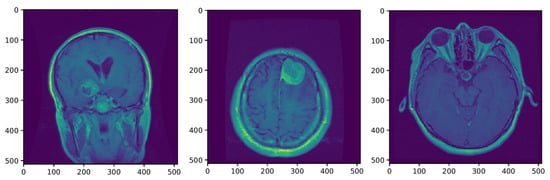

To help distinguish the tumor tissue and more precisely determine the tumor borders, the patients are typically injected with a contrast solution (Gadolinium). These images can be utilized in the classification of the tumor grade. Figure 4 shows axial MRIs with Gadolinium infusion of three grades of glioma brain tumors. Finally, Figure 5 shows three brain tumor cases from the second dataset utilized in this research [81]. As mentioned, all employed images were normalized to the [ 0 , 1 ] interval, and their dimension was set to 128 × 128 pixels.